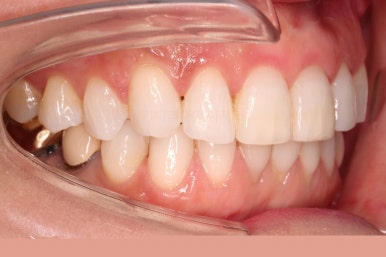

초진 시 입안의 모습입니다.

환자분이 원하셨던 부분은 윗니 작은 앞니가 하나 튀어나와서 개선하고 싶어하셨습니다.

부가적으로 아랫니 앞니가 마모가 심하여 높낮이가 달라보이는 점이었는데요.

초진 시 얼굴 모습입니다.

전반적으로 모두 양호합니다. 입이 편안하게 다물어지는 느낌, 옆라인, 심지어는 중앙선까지 양호합니다.

단 하나, 작은 앞니 하나가 톡 튀어나와 있는 부분이 미적으로 좋지 못한데요.